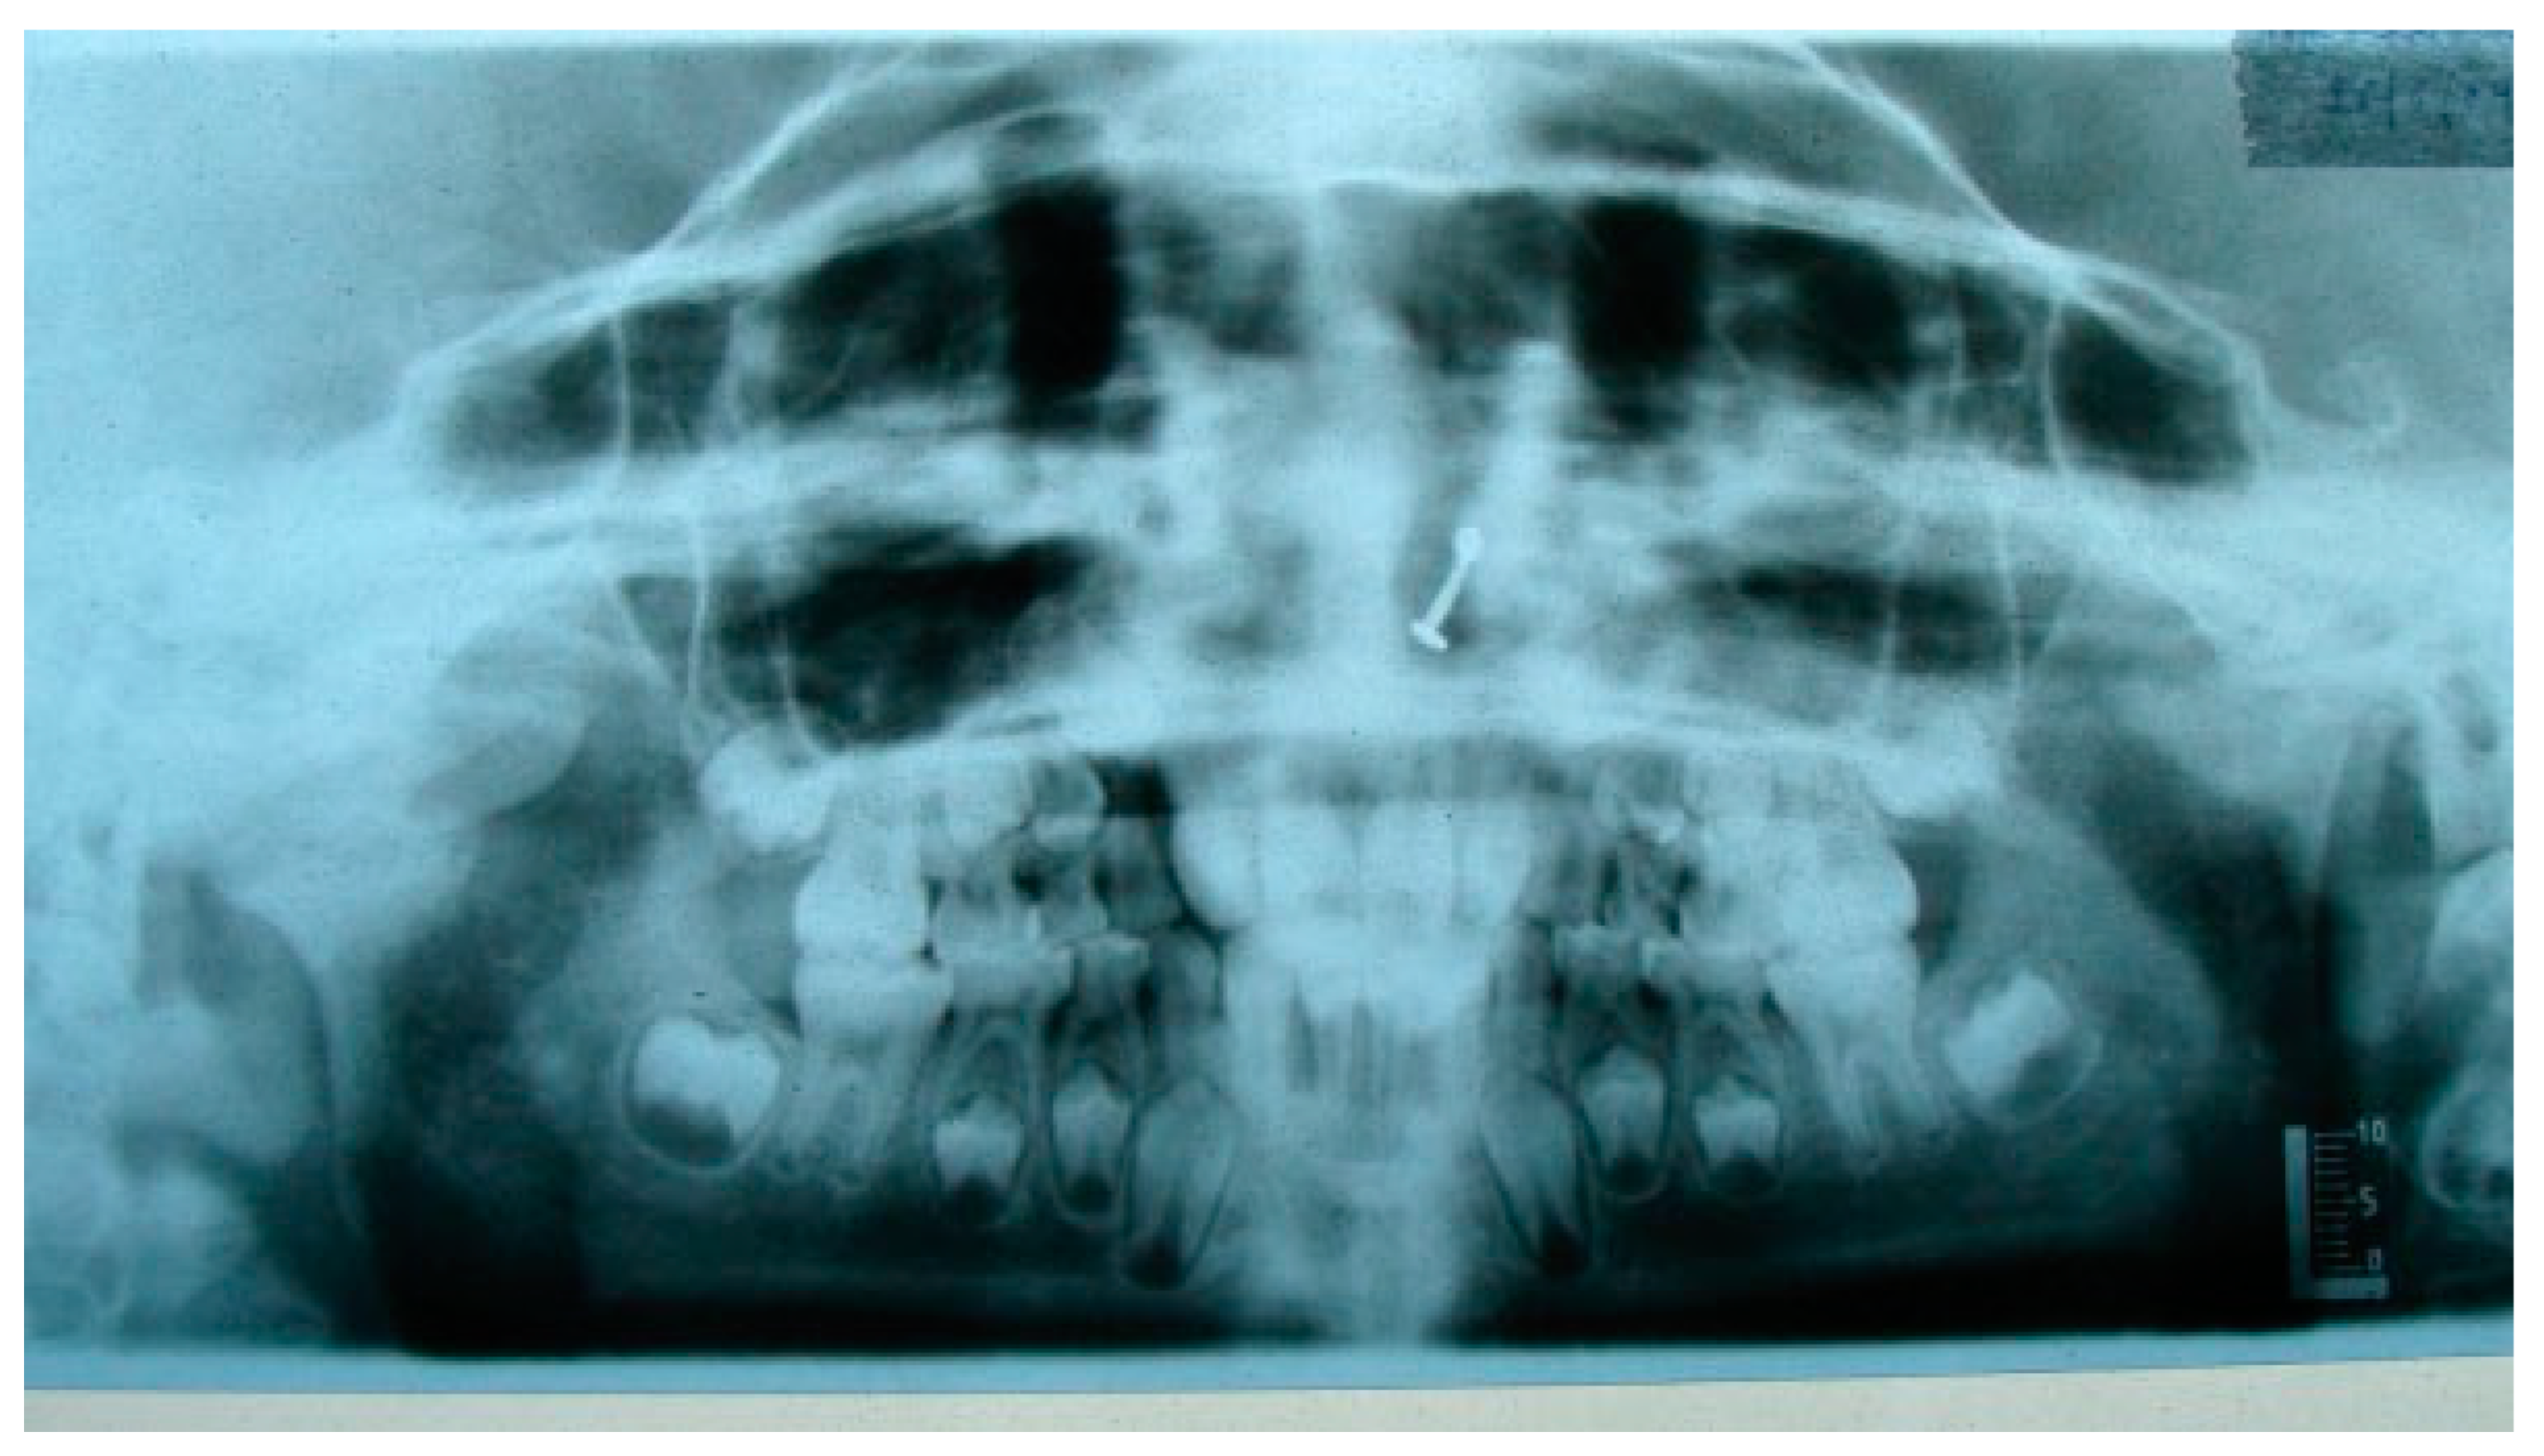

A retrospective study of post–ankylotic TMJ reconstruction of all the patients who underwent surgery for the TMJ ankylosis over a period of 11 years from 2002 to 2013, which were operated by the senior author (Y.B.), was undertaken to evaluate demographics, type of TMJ ankylosis, and modality of post–ankylotic TMJ reconstruction. The following inclusion criteria were considered for enrolling patients in this study: (1) history of traumatic injury to the face or jaws; (2) clinical and radiographic evidence of bony ankylosis at the time of presentation; (3) reconstruction of the TMJ using autogenous or alloplastic material after surgical release of ankylosis. Patients were assessed for (1) maximum interincisal opening pre and post operatively; (2) restored vertical ramal height; (3) occlusion; (4) facial symmetry; and (5) postoperative complications. Radiographic evaluation consisted of both preoperative and postoperative panoramic radiography Orthopentomogram (OPG) (Figure 1 and Figure 2) and CT scans in axial, coronal, and sagittal sections with three-dimensional reconstruction (Figure 3 and Figure 4). Surgical protocol was that the TMJ was approached through the Al-Kayat and Bramley’s incision and at least 2 to 2.5 cm resection of the ankylotic chunk was performed in all our cases. Ipsilateral and contralateral coronoidectomy was performed when required to achieve passive mouth opening. Interpositional arthroplasty was done using various materials such as temporalis fascia, temporalis muscle, and articular disc, whereas joint reconstruction was done using CCG and titanium reconstruction plate with condylar head. Intensive physiotherapy postoperatively was an integral part of protocol.

Figure 1. Preoperative OPG of right temporomandibular joint ankylosis.